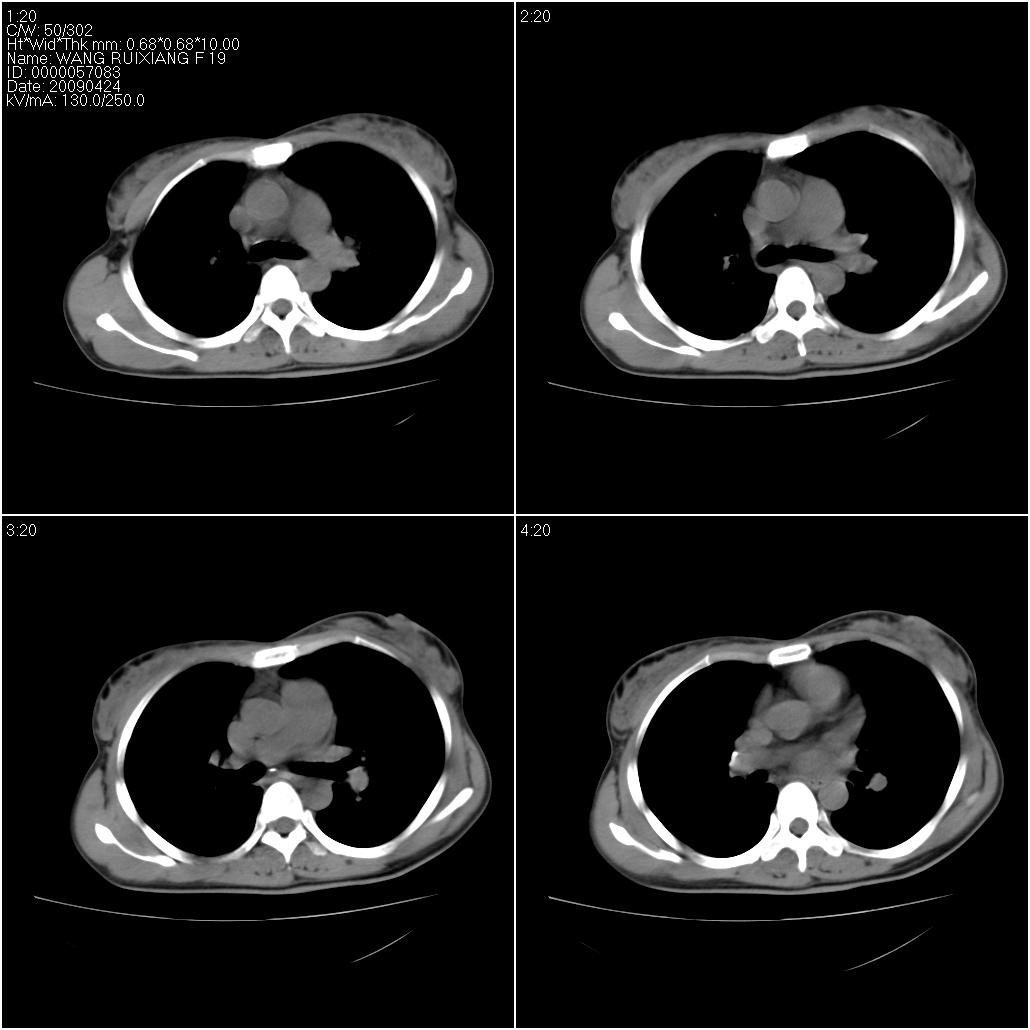

标题: CT19588:女性,39岁。患者胸闷不适,上楼时气喘。 [打印本页]

标题: CT19588:女性,39岁。患者胸闷不适,上楼时气喘。

片子上的年龄为19岁,是操作错误。该患者于去年5月份曾做平片和ct扫描,和这一次的ct检查没有明显变化。当时诊断为肺结核,进行抗痨治疗至今,但没有改善。呼吸功能试验为混合型呼吸困难。除此之外,该患者没有其他方面没有的临床症状和体征

两肺见斑点片状阴影,部分病灶密度较高,右下肺见小囊状及柱状蜂窝状阴形,考虑为两肺结核以阵旧性为主,右下肺支扩。

1)两肺继发性肺结核(以增殖病灶为主)。2)两肺下叶支气管扩张。

1)两肺继发性肺结核(以增殖病灶为主)。

2)两肺下叶支气管扩张。